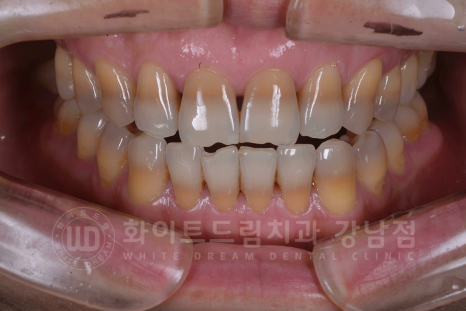

▲ 강남역 인근 치과, 강남 화이트드림치과 전치부 라미네이트 후

환자분은 14 - 24 / 34 - 44까지의 총 8개의 치아를 라미네이트로 진행하셨습니다.

동일 인물이며, 동일 환경에서 촬영되었습니다. / 강남역 인근 치과

(치료 기간 : 23.12.11 - 23.12.18)

테트라사이클린으로 인한 치아 변색이 심할 경우는 크라운까지 고려되지만,

오늘 알려드린 사례자 분과 비슷한 정도의 변색이라면 간단하게 라미네이트로 드라마틱한 개선이 가능하답니다. ^^

40년 동안 어두운 치아로 너무 스트레스였어요.

제일 밝은색의 치아로 만들어 주세요!

라는 환자분의 요청에 맞추어 상담 후 제일 밝은 색상의 보철로 제작을 하였습니다.

동일 인물이며, 동일 환경에서 촬영되었습니다.

※ 무보정입니다!

치아 색상만 바뀌었는데도 피부나 인상이 환해진 것을 확인할 수 있습니다. ^^